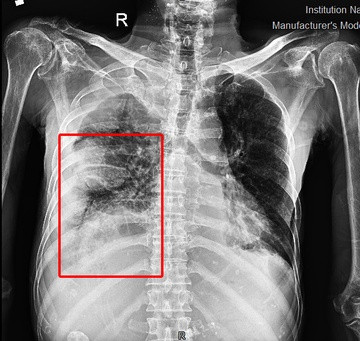

Tiếp nhận bệnh nhân, bác sĩ Khoa Cấp cứu, Bệnh viện Đa khoa Đức Giang (Hà Nội) phát hiện tình trạng tràn mủ phổi phải cùng nhiều ổ áp xe, đông đặc thùy dưới phổi trái, chẩn đoán bệnh nhân hôn mê, suy hô hấp cấp.

Kết quả chụp CT cho thấy hình ảnh tràn dịch khoang màng phổi 2 bên gây xẹp thụ động nhu mô phổi lân cận, giãn các nhánh phế quản phải trong vùng nhu mô phổi xẹp. Bệnh nhân cũng xuất hiện hạch trung thất và hạch hố thượng đòn phải.